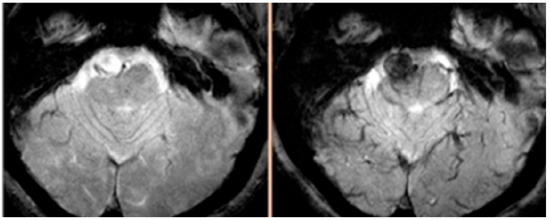

- Dosa, E.; Tuladhar, S.; Muldoon, L.L.; Hamilton, B.E.; Rooney, W.D.; Neuwelt, E.A. MRI using ferumoxytol improves the visualization of central nervous system vascular malformations. Stroke 2011, 42, 1581–1588. [Google Scholar] [CrossRef]